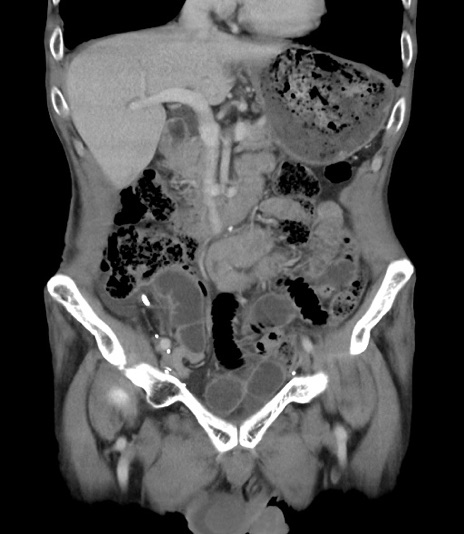

症例3(冠状断像)

【症例】 70歳代男性

【主訴】右鼠径部腫瘤、疼痛

【現病歴】本日朝より上記主訴あり、受診。

【既往歴】膀胱癌にて膀胱全摘、両側尿管皮膚瘻

【データ】WBC 5600、CRP 0.56